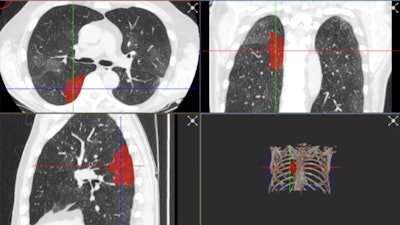

The added difficulty of COVID-19 lung abnormalities is they can be subtle and difficult to differentiate from other conditions. Last week, for example, Ranschaert and his colleagues at the Elisabeth-TweeSteden Hospital in Tilburg, the Netherlands, treated a patient with a pneumocystis carinii pneumonia infection. As in COVID-19 cases, this infection can give similar opacification on both sides of the lungs, so it requires great care and can be misdiagnosed, he pointed out.

"In this phase of the crisis, we see typical abnormalities and everybody assumes straight away that this is COVID-19, but we have to keep in mind this is not always the case," he said. "When developing an AI tool, we have to have a good, balanced data set. This means there must be a controlled data set that shows other, similar kinds of pathologies so the AI tool can provide a good probability score that this is COVID-19 or not."

For training an algorithm, he thinks chest CT images with a slice thickness of 3 mm or less provide sufficient image quality.